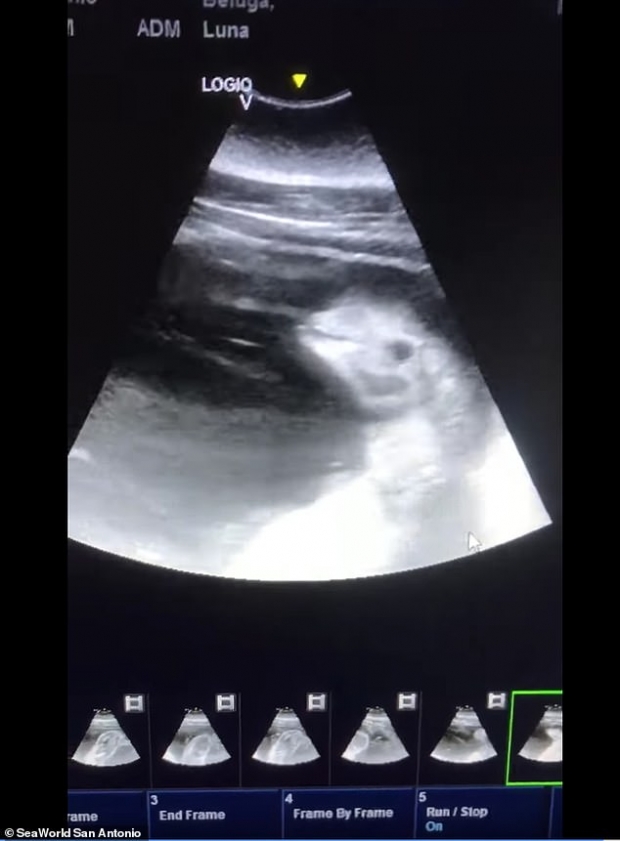

KSAT 등 현지매체 보도에 따르면, 텍사스주(州) 관광명소 ‘시월드 샌안토니오 지점’은 지난 11일(현지시간) 페이스북을 통해 암컷 벨루가 루나(Luna)의 배 속 태아를 촬영한 초음파 영상을 공개했다.

이에 대해 공원 측은 “어미는 ‘허즈번드리 트레이닝’(husbandry training)으로 불리는 특수 훈련을 받은 덕분에 수의팀이 검사하는 동안 가만히 있을 수 있어 초음파 영상을 기록할 수 있었다”고 설명했다. 허즈번드리 트레이닝은 동물원 등에서 멸종 위기에 처한 동물 등을 보존하기 위한 노력의 일부분으로 행하는 훈련 방법을 말한다.

공원 측은 또 “우리는 루나의 임신 소식을 공유하게 돼 매우 기쁘고 앞으로 새끼 벨루가를 시월드 가족으로 맞이할 날을 기대하며 어미를 24시간 내내 보살필 계획”이라고 밝혔다. 초음파 영상 속 새끼 벨루가는 오는 가을쯤 태어날 예정이다.